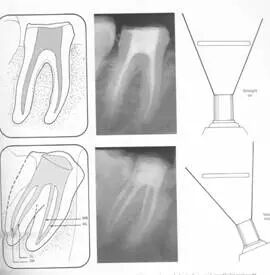

一、根管充填的步骤

1. 主牙胶尖的确认

由于器械磨损或生产误差影响,主牙胶尖与实际型号可能存在一定偏差,需要进行测量确认。

( 1 )通过带有孔径的量尺选择主牙胶尖。

1 )器械的选择:选择器械作为中锉,插入量尺孔中。器械正好插入小孔,下面刚刚能够触到,该小孔为器械合适直径的小孔。

2 )牙胶尖的选择:选用稍微细点的牙胶尖插入,孔背面切平,获得的牙胶尖端直径和中锉直径一致。

( 2 )牙胶直径合适后确认长度,获得主牙胶,然后选择主牙胶尖。

主牙胶尖插不进去表明主牙胶尖有些粗;插到外面去表明主牙胶尖有些细。通过反复筛选,选择刚好可以卡在里面的牙胶尖,完成主牙胶尖的确认。

左图为 ISO 标准 20 号牙胶尖,黄颜色。图中从左向右依次为 02 、 04 、 06 锥度。

右图为 ISO 标准 25 号牙胶尖,红颜色,尖端直径为 0.25mm 。图中从左向右依次为 02 、 04 、 06 锥度。

左图为 ISO 标准 30号牙胶尖,蓝颜色。图中从左向右依次为 02 、04 、06 锥度。

2. 糊剂的导入

选好牙胶尖后开始根管充填,侧方加压术中可使用螺旋充填器导入糊剂。不要把螺旋充填器一直放在根尖狭窄部位置,避免糊剂超填,造成治疗失败。

螺旋充填器正确的使用步骤:螺旋充填器固定在距根尖孔 4-5mm 位置,进行旋转输送。然后用牙胶尖或光环 C 针做全长轻轻提拉,再使用螺旋充填器进行输送,保证根尖下端的填充。

3. 主牙胶尖的插入

主牙胶尖应提拉插入,以避免超填。

主牙胶尖常选择 02 锥度主牙胶尖,有下面几个优点:( 1 )能够很好地到达根尖狭窄部。( 2 )侧方加压时有较大空间,封闭型好。

4. 辅牙胶尖的插入

主牙胶尖插后选择侧方加压器进行侧方加压根管充填。

( 1 )侧方加压器的选择:

术前应选择好,直径为到达距根尖狭窄部2 -3mm 位置,避免将主牙胶尖挤压出根尖狭窄部。

( 2 )操作:加压时冲牙胶位置挤压,拿出侧方加压器后立即插入辅牙胶尖。

金属器械取出时牙胶尖有回弹,如果辅牙胶尖放置时间过长,不能到达侧方加压位置,可能造成中间空隙。可在牙胶尖上蘸一些糊剂送入。关键是迅速插入辅牙胶尖。

5. 致密加压

插入辅牙胶尖后,去除多余牙胶,使用垂直加压器垂直致密加压。

操作:进行完根管充填、牙胶放好后,使用垂直加压器,从根管口向根管方向垂直加压,压入 1-2mm 。

优点 :封闭冠,预防牙冠方的的细菌感染。

6. 术后 X 线片

术后 X 线片用来评定根管充填 长度、致密度(管壁清晰、侧枝)等指标。

左图为根管充填术后 X 线片。图中可见,根管充填较好。右下图有白色小点,为侧方加压导致糊剂挤出所致,表明根管充填比较致密。